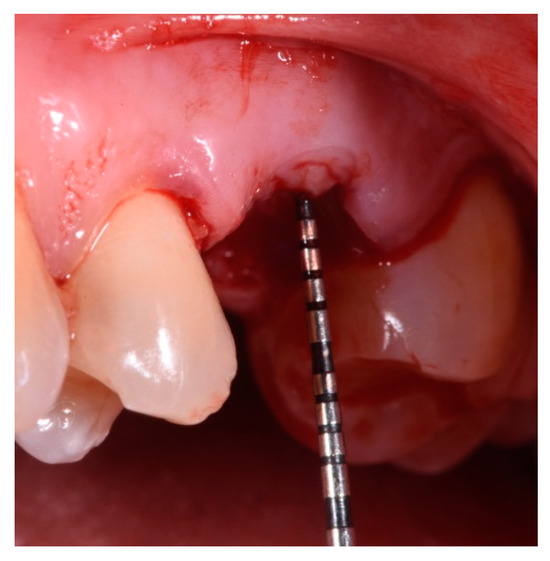

- Periodontal probing to assess the presence of the buccal plate.

- Measurement in mm of the depth of insertion of the instrument into the gingival sulcus;